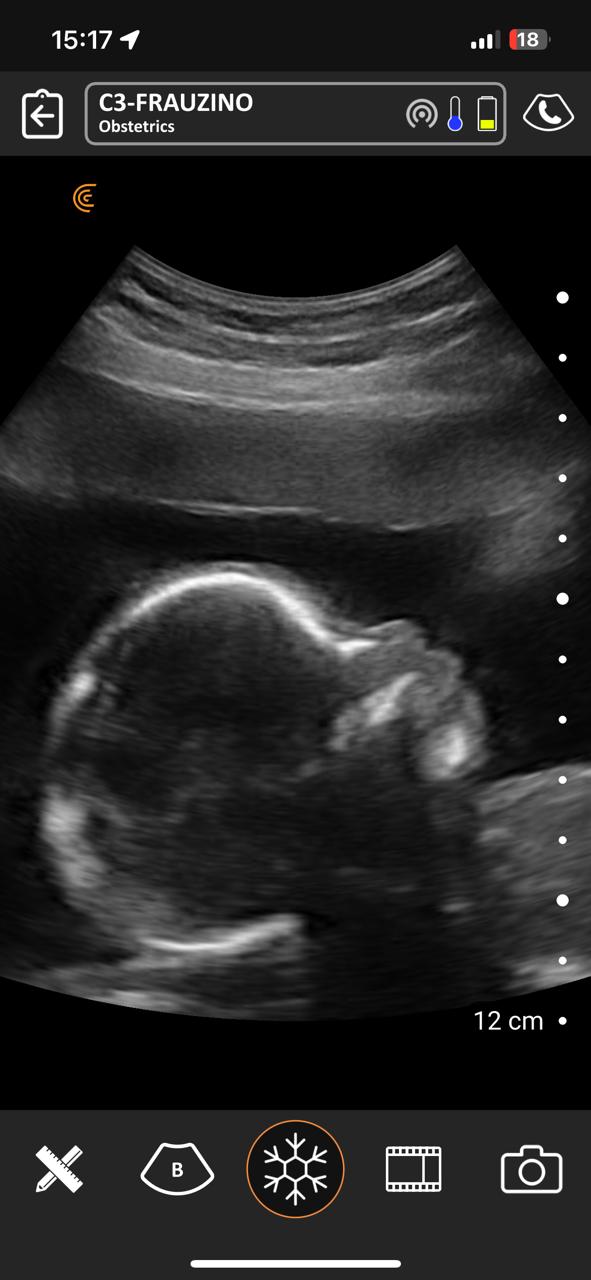

No período compreendido entre 07/03/2023 a 07/03/2025 na Estratégia de Saúde da Família São Francisco ESF-03 e Sol Nascente ESF-07 no município de Porangatu (GO), Brasil realizou-se um total de 8.349 atendimentos médicos, com 769 consultas de pré-natal e 411 ultrassons no local de atendimento de acompanhamento do pré-natal de risco habitual com aparelho portátil de bolso, sem fio, tecnologia Clarius C3 HD3, transdutor convexo, frequência de 2-6 MHz e monitores iPhone-10 e iPad Air 11. Acompanharam alguns atendimentos 12 bolsistas do PMpB dos municípios goianos Bonópolis, Britânia, Campinorte, Mara Rosa, Mundo Novo, Mutunópolis, Niquelândia, Nova Veneza, Santa Tereza de Goiás, São Miguel do Araguaia e do Pará Santana do Araguaia. Os bolsistas não tinham conhecimentos prévios sobre a PoCUS, disseram que sua formação nessa ferramenta durante o PMpB foi satisfatória e caso tivessem um aparelho sentem confiança em realizar o procedimento tanto na Unidade Básica de Saúde quanto nos domicílios, acreditaram que a formação básica recebida foi alcançada e concordam totalmente que a ultrassonografia no local de atendimento poderia estar dentro da formação especializada em medicina de família e comunidade e entenderam que no pré-natal de risco habitual é uma ferramenta que pode mudar sua conduta.

Nos acompanhamentos das consultas de pré-natal, dos 411 ultrassons realizados, 19 foram de diagnóstico gestacional e datação da idade gestacional, sendo 13 com idade gestacional menor de 14 semanas, uma na 24ª e outra na 29ª semana. Houve duas gestações gemelares que foram acompanhadas conjuntamente com o alto risco. A média de idade das gestantes foi de 26 anos e o da idade gestacional de 22 semanas e 2 dias. Os bolsistas realizaram um total de 188 ultrassons e após a familiarização teórica e prática, foram capazes de identificar 10 tópicos como situação, apresentação, dorso, batimento cardíaco fetal, movimentos fetais, órgãos internos (ao menos 1 estrutura), biometria (ao menos diâmetro biparietal e comprimento do fêmur), placenta, líquido amniótico, cordão umbilical, datar e descrever o procedimento.